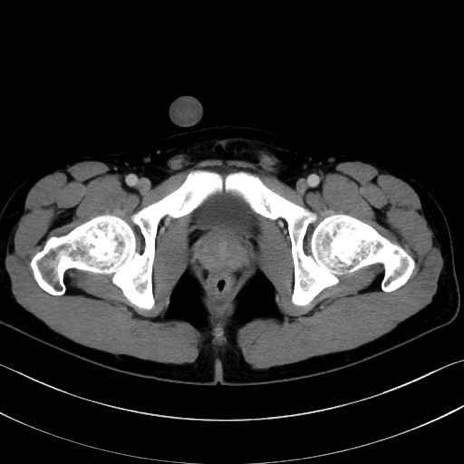

小殿筋 (Gluteus minimus)